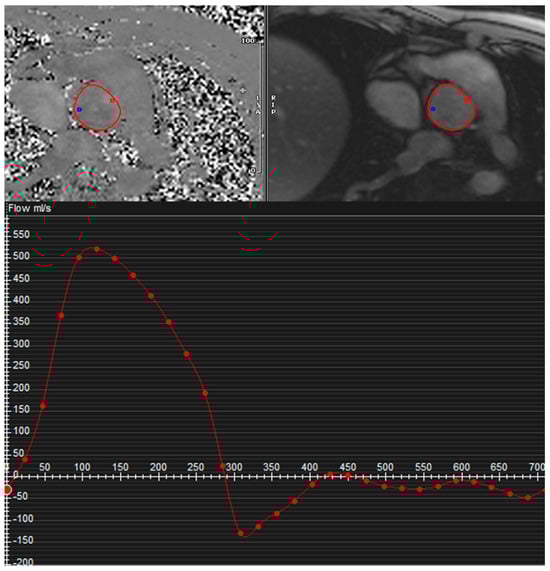

3.1. Quantitative Assessment

- Muzzarelli, S.; Monney, P.; O’Brien, K.; Faletra, F.; Moccetti, T.; Vogt, P.; Schwitter, J. Quantification of aortic flow by phase-contrast magnetic resonance in patients with bicuspid aortic valve. Eur. Heart J.—Cardiovasc. Imaging 2014, 15, 77–84. [Google Scholar] [CrossRef]